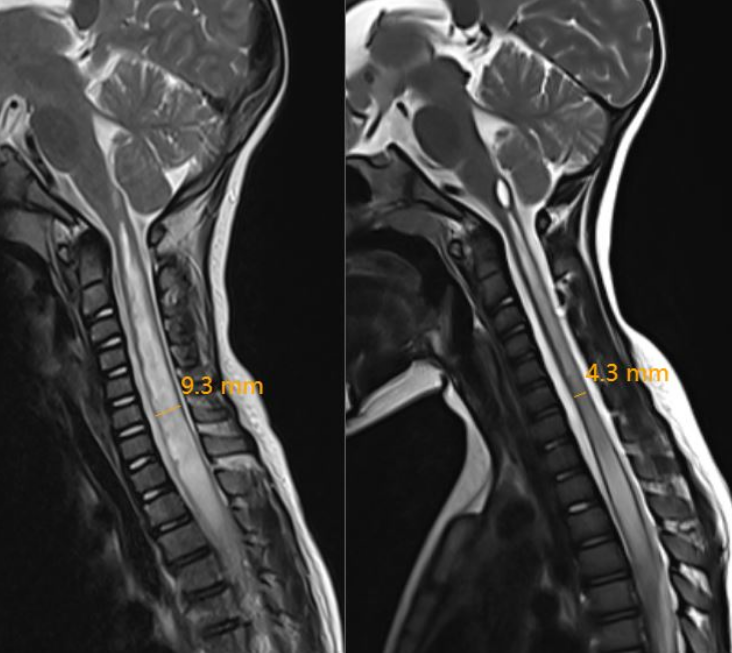

娄永利根据菲菲的情况制定了适合她的手术方案,并给出后续的治疗和康复措施。菲菲的父母听后,决定为孩子进行微创的终丝松解术,手术切口仅1.5cm。仅仅在术后第5天,再次对比同一节段的空洞已经从9.3毫米缩小至4.3毫米,短短的5毫米让菲菲的左手再一次明显感受到了这个世界的冷暖,她终于和其他孩子一样了。